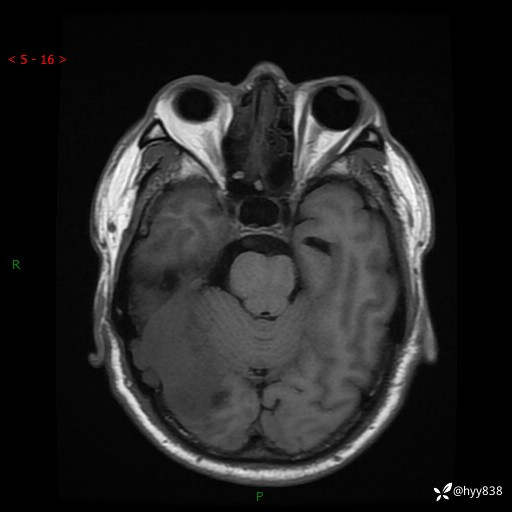

患者性别:男

患者年龄:56岁

简要病史:外院CT提示脑膜瘤,为进一步诊治来我院

辅助检查:MRI

临床诊断:颅脑占位

颅脑MRI平扫+增强